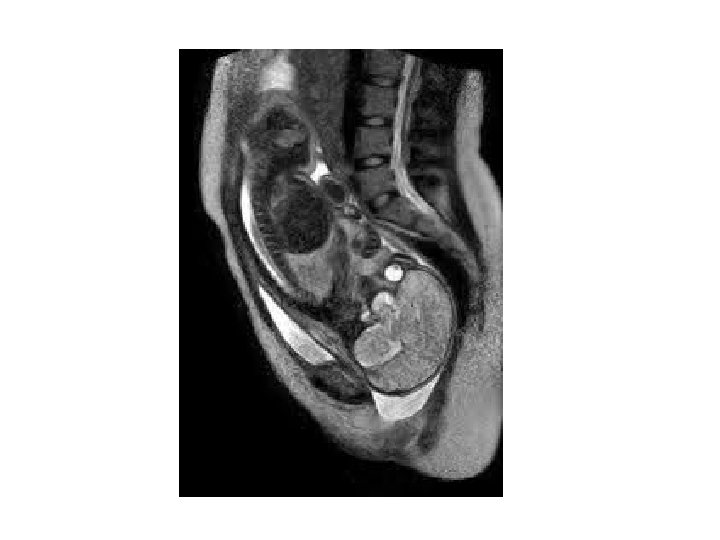

Dislocation Reduction Retention 4 weeks later